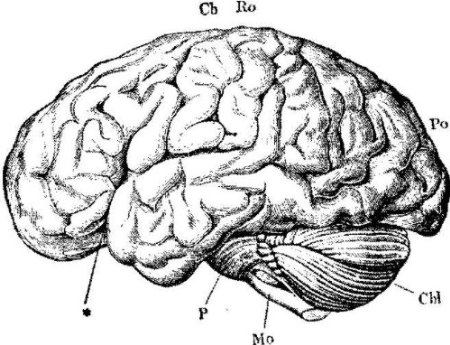

Anatomical Heart Drawing

1063x1390 Human Heart Sketch. Anatomical Heart Organ Etching Drawing

722x900 Heart Anatomy, 18th Century Photograph By